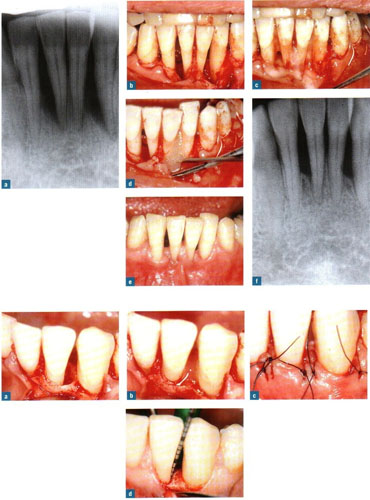

rejeneratif periodontoloji ameliyatı

ilerlemiş dişeti hastalığı sonucunda dişin içinde oturduğu kemik (alveol kemiği) iltihabi olaylar sonucu erimeye başlar ve belli bir süre sonra dişte sallanmalar (mobilizasyon) yer değiştirme görülür.

Ayrıca genel ve lokal dişeti abseleri oluşabilir. Bu sorunun tedavisinde dişetinin açılarak dişik kök yüzeyinin temizlenmesi, civardaki iltihaplı dokunun (granülanyon dokusu) temizlenmesi ve kliniğimizde uyguladığımız yöntemle, o boşluklara yapay kemik + minematriks proteini (Emdogain (R) ) uygulaması yapılarak 6-8 ay sonra operasyon bölgelerinde yeniden alveol kemiği oluşumu sağlanmakta ve bu yolla belkide çekilecek bir diş ağızda tutulmaktadır.

1) Dişeti cebinde azalma 2) Dişeti iltihaplarının ortadan kalkması 3) Ataşman (dişetinin yeniden dişe yapışması) kazancı da operasyonun başarısının kanıtı olarak ortaya çıkar.